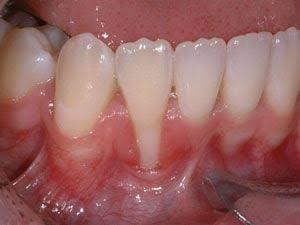

- Gum Diseases - Gum diseases can be roughly classified into 2 categories: - 1. Gingivitis - a reversible form of gum disease caused by dental plaque, usually appears as bleeding when brushing and redness of gums - 2. Periodontitis* - an irreversible, advanced form of gum disease that involves pocket formation, gum recession and bone loss, resulting in mobility and subsequent loss of teeth  - Risk factors including genetics, poor oral hygiene, smoking and poorly controlled diabetes can increase the risk of development/severity of gum diseases/treatment outcome. - *Requires ongoing reviews and further management by dental practitioners  - A periodontal chart is required to understand the extent and severity before intervention.  - Advanced gum disease with heavy calculus/tartar deposits and gum recession: gums appear red and swollen.